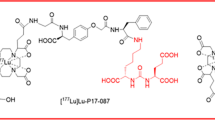

More recently, a PSMA ligand with a p-tolyl-entity was developed [14], in order to reduce the strong affinity to serum albumin and eventually optimize its pharmacokinetic profile [25]. Indeed, the tumor accumulation of [177Lu]Lu-PSMA-ALB-56 in mice was higher than for [177Lu]Lu-PSMA-617, while background retention was relatively low. The resulting efficacy of [177Lu]Lu-PSMA-ALB-56 for the treatment of PSMA-positive PC-3 PIP tumor-bearing mice was significantly improved as compared with that of the same activity of [177Lu]Lu-PSMA-617 [25].

Our study was the first clinical application of [177Lu]Lu-PSMA-ALB-56, which is modified with a p-tolyl-entity as an albumin-binding entity. The aim of increasing the accumulation of activity in tumor lesions was successfully achieved. It resulted in a 1.4–2.3-fold higher absorbed dose to tumor lesions (6.64 Gy/GBq) as compared with published values for [177Lu]Lu-PSMA-617 (3.87 Gy/GBq [37], 4.60 Gy/GBq [38], and 2.80 Gy/GBq [39]) and [177Lu]Lu-PSMA I&T (3.30 Gy/GBq [40] and 3.20 Gy/GBq [41]), respectively.